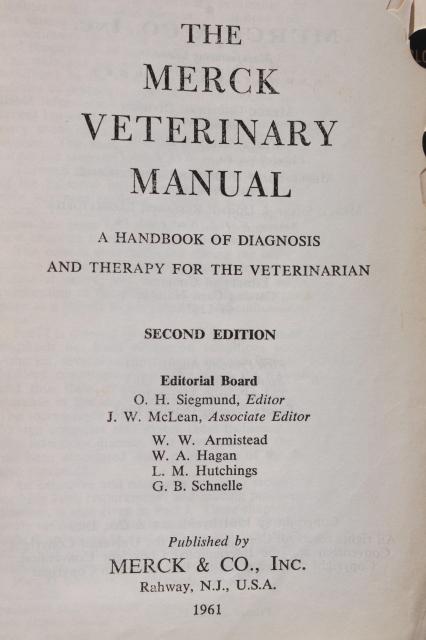

Vintage Merck Manual Medical Book, 2nd Edition Merck Veterinary Manual 1961

www.laurelleaffarm.com

www.laurelleaffarm.com

merck veterinary manual 1961 2nd edition medical